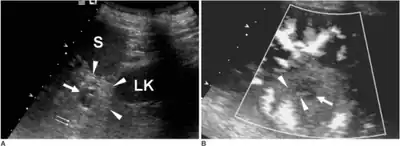

Ultrasound image of intrapancreatic accessory spleen